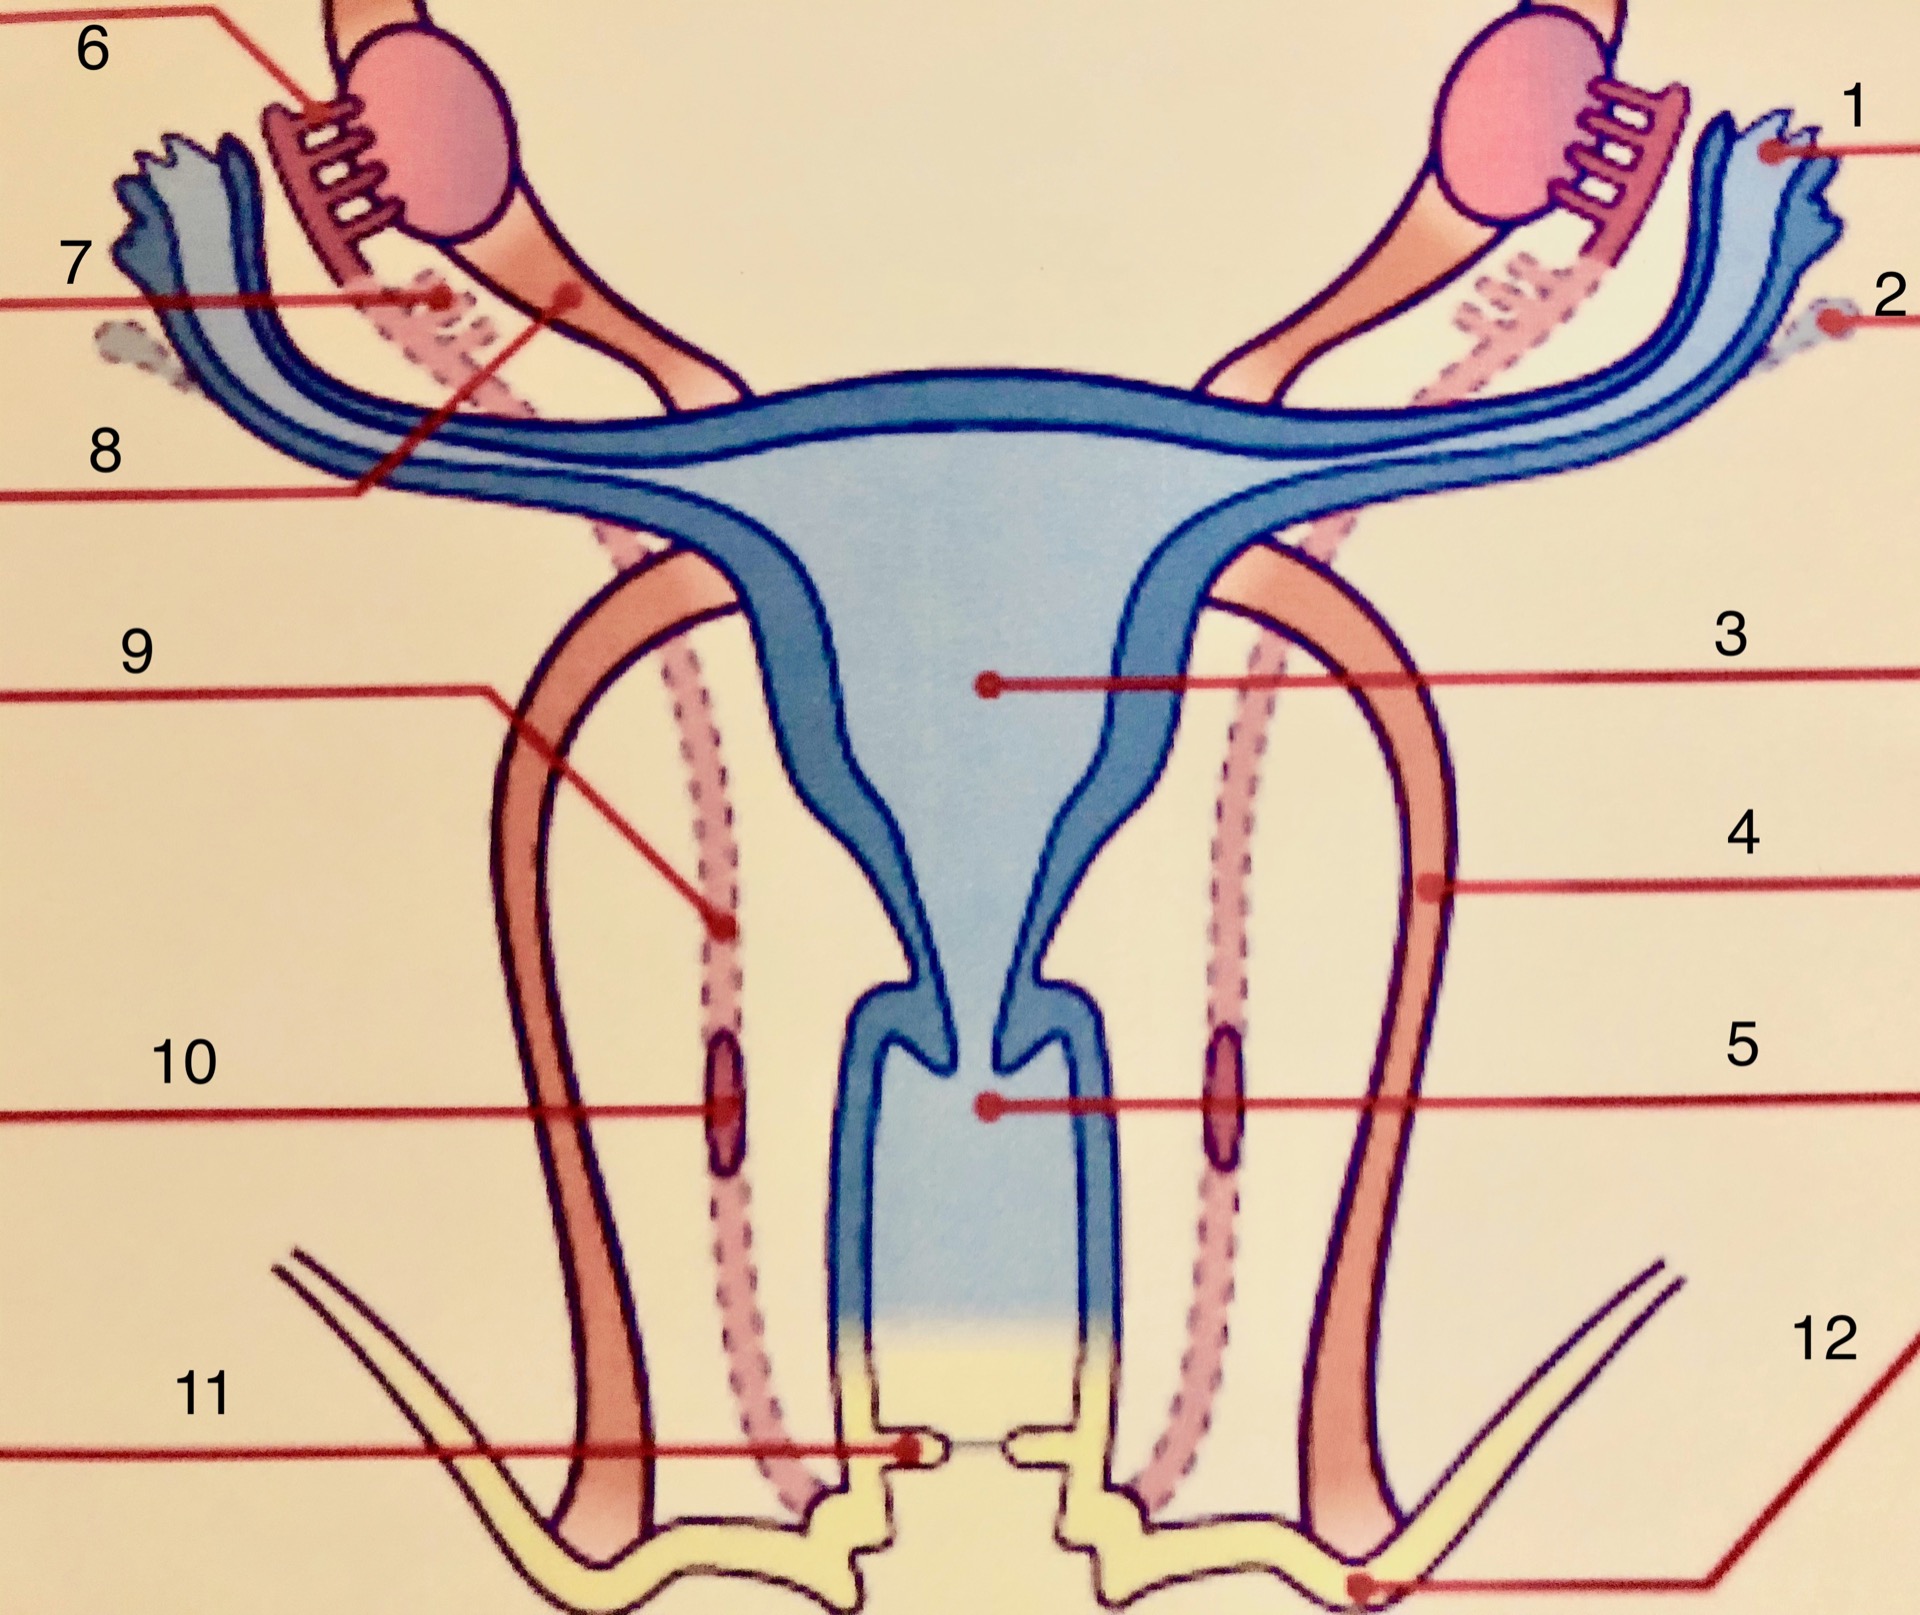

Normální tvar a vývoj dělohy

1. vejcovod, 2. cystický přívěšek, 3. děloha, 4. vaz, 5. pochva, 6., 7., 9., 10. zbytky Wolfova vývodu, 8. závěs vaječníku, 11. panenská blána, 12. úpon vazu

Vývojové vady dělohy jsou výsledkem poruch vývoje Müllerových vývodů, jejich kanalizace, splynutí nebo vstřebání středové části. Jsou omezené pouze na děložní tělo, ale mohou postihovat i děložní hrdlo a pochvu